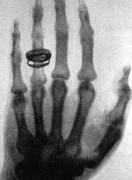

Corría el año 1895 y Wilhelm Röntgen estaba obsesionado con unos rayos invisibles que atravesaban el cartón. Un día, con esa emoción que solo tienen los científicos cuando están a punto de cambiar el mundo, llamó a su esposa, Anna Bertha Ludwig, al laboratorio. —... + más